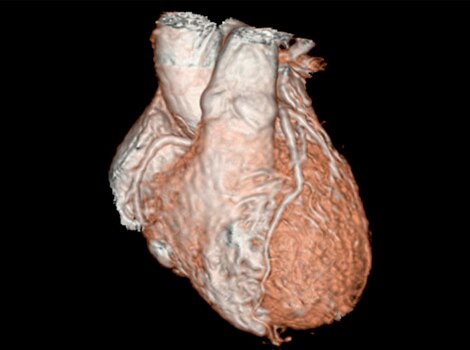

3D Heart

Visualize the anatomical structures and vascularity of the heart with a bright blood, 3D sequence.

Read More

Revolution CT & CardioGraphe4

Achieve one-beat, whole heart acquisition for imaging or comprehensive cardiac assessment with or without beta blockers at any heart rate.5

Visualize the anatomical structures and vascularity of the heart with a bright blood, 3D sequence. Read More